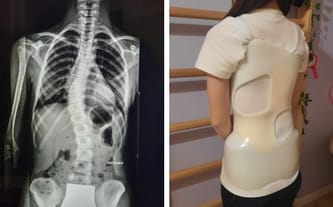

Choroba odbiera jej marzenia❗️Pomagamy Blance❗️

Idiopatyczna skolioza młodzieńcza